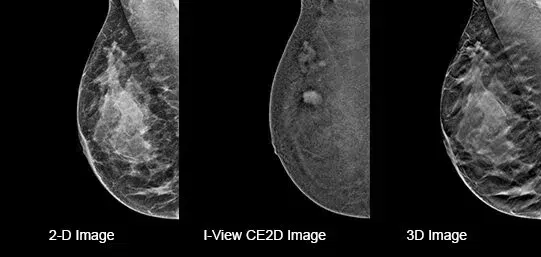

Capture a pair of high and low energy images in rapid succession. This enables visualization of areas with abnormal blood flow by subtracting the breast parenchyma background.